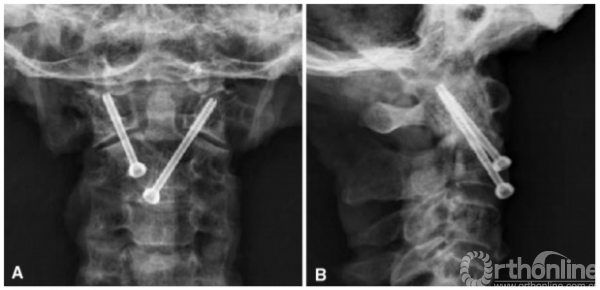

所有标本均成功完成ATCS和ATS固定,未见C1椎动脉沟、椎管及寰枕关节损伤。ATCS和ATS实际进钉点与中线的侧方距离分别为5.0±1.1mm和13.0±1.5mm。ATCS固定理想的外展角和倾斜角分别为38.3±4.1°和30.7±2.9°,而ATS分别为29.6±2.7°和34.3±2.5°。理想螺钉角度与实际螺钉角度无统计学差异(P<0.05)。螺钉置入后(图4),x线测量ATCS相对矢状面实际外展角大于ATS。然而,ATCS相对于冠状面的实际倾斜角小于ATS(表3)。

图4前路经关节交叉螺钉固定前后位x线片(a)和侧位片(b)视图

C1/C2的螺钉长度及钉道长度汇总见表3。总体上ATCS的螺钉长度(40.4±2.2mm)明显大于ATS(26.4±3.1mm)(P<0.001)。ATCS固定在C1骨质内的钉道长度为14.8±1.6mm,与ATS相似(14.9±1.5mm)。但ATCS在C2骨质内的钉道长度为25.6±1.6mm,明显大于ATS的11.4±1.7mm(P<0.001)。

The ATCS and ATS were inserted successfully into all specimens without any violation to the VA groove of C1and C2, or the spinal canal. Neither was there any violation to the atlanto-occipital joint. The actual entry points of ATCS and ATS lateral from the midline was 5.0 ± 1.1 mm and 13.0 ± 1.5 mm, respectively. The ideal lateral and incline angles were 38.3 ± 4.1 and 30.7 ± 2.9 for the ATCS, and 29.6 ± 2.7 and 34.3 ± 2.5 for the ATS, respectively. There was no statistical difference between the ideal and the actual screw angulations (p<0.05). After the screws were inserted (Fig. 4), the actual lateral angle of the ATCS relative to sagittal plane was greater than that of the ATS measured on anteroposterior X-rays. On the contrary, the actual incline angle of the ATCS relative to coronal plane was smaller than that of the ATS (Table 3).

Fig. 4 The anterior transarticular crossing screws fixation is shown on anteroposterior (a) and lateral radiographs (b), respectively

The screw lengths and lengths of C1/C2 purchase were summarized in Table 3. Overall, the ATCS length (40.4 ± 2.2 mm) was significantly longer than the ATS length (26.4 ± 3.1 mm) (p<0.001). The ATCS length of C1 purchase was 14.8 ± 1.6 mm, and similar to the ATS length (14.9 ± 1.5 mm). The ATCS length of C2 purchase was 25.6 ± 1.6 mm, and longer than the ATS length (11.4 ± 1.7 mm) (p<0.001).